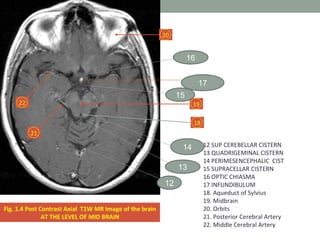

Fig. 1.4 Post Contrast Axial T1W MR Image of the brain

AT THE LEVEL OF MID BRAIN

12 SUP CEREBELLAR CISTERN

13 QUADRIGEMINAL CISTERN

14 PERIMESENCEPHALIC CIST

15 SUPRACELLAR CISTERN

16 OPTIC CHIASMA

17 INFUNDIBULUM

18. Aqueduct of Sylvius

19. Midbrain

20. Orbits

21. Posterior Cerebral Artery

22. Middle Cerebral Artery

Fig. 1.4 PostContrast Axial T1W MR Image of the brain AT THE LEVEL OF MID BRAIN 18 19 20 21 22 12 SUP CEREBELLAR CISTERN 13 QUADRIGEMINAL CISTERN 14 PERIMESENCEPHALIC CIST 15 SUPRACELLAR CISTERN 16 OPTIC CHIASMA 17 INFUNDIBULUM 18. Aqueduct of Sylvius 19. Midbrain 20. Orbits 21. Posterior Cerebral Artery 22. Middle Cerebral Artery 17 16 15 12 13 14